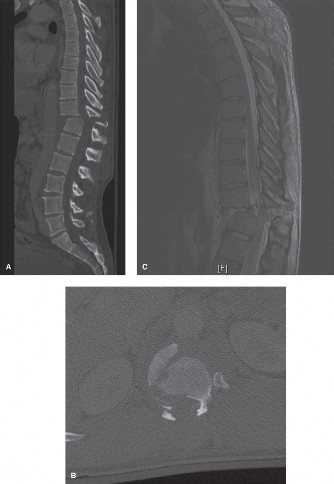

When surgical intervention becomes unavoidable, meticulous pre-operative planning is the cornerstone of a successful outcome. Advanced imaging is non-negotiable. An MRI with and without gadolinium contrast is the gold standard for defining the extent of the epidural abscess, the degree of neural compression, and the involvement of adjacent paraspinal musculature (e.g., psoas abscess). T1-weighted images typically show hypointense signals in the infected marrow, while T2-weighted and STIR sequences reveal hyperintense fluid and edema in the disc space and vertebral bodies. Gadolinium enhancement highlights the vascularized inflammatory phlegmon and the capsule of any abscesses.

In addition to MRI, a fine-cut computed tomography (CT) scan is essential for evaluating bony destruction. CT allows the surgeon to assess bone stock for pedicle screw purchase and to template the size of the interbody cages required for anterior column reconstruction. Upright standing radiographs (if the patient can tolerate them) or full-length supine films are necessary to evaluate global spinal alignment and regional kyphosis.

A radical discectomy is performed. All necrotic disc material, infected cartilaginous endplates, and sequestered bone must be aggressively removed using curettes, pituitary rongeurs, and high-speed burrs until punctate bleeding from healthy cancellous bone is encountered. This aggressive debridement is critical for eradicating the bacterial biofilm and providing a vascularized bed for subsequent fusion. Copious irrigation with sterile saline (often several liters) is employed to mechanically wash out residual bacterial load.

Following debridement, a large void is left in the anterior column. To restore disc height, correct kyphosis, and provide structural support, an interbody device must be inserted. Historically, autologous tricortical iliac crest bone graft was the gold standard. However, structural allografts and titanium cages have been proven safe and highly effective even in the setting of active pyogenic infection, provided that the debridement is thorough and the patient is maintained on appropriate culture-directed antibiotics.